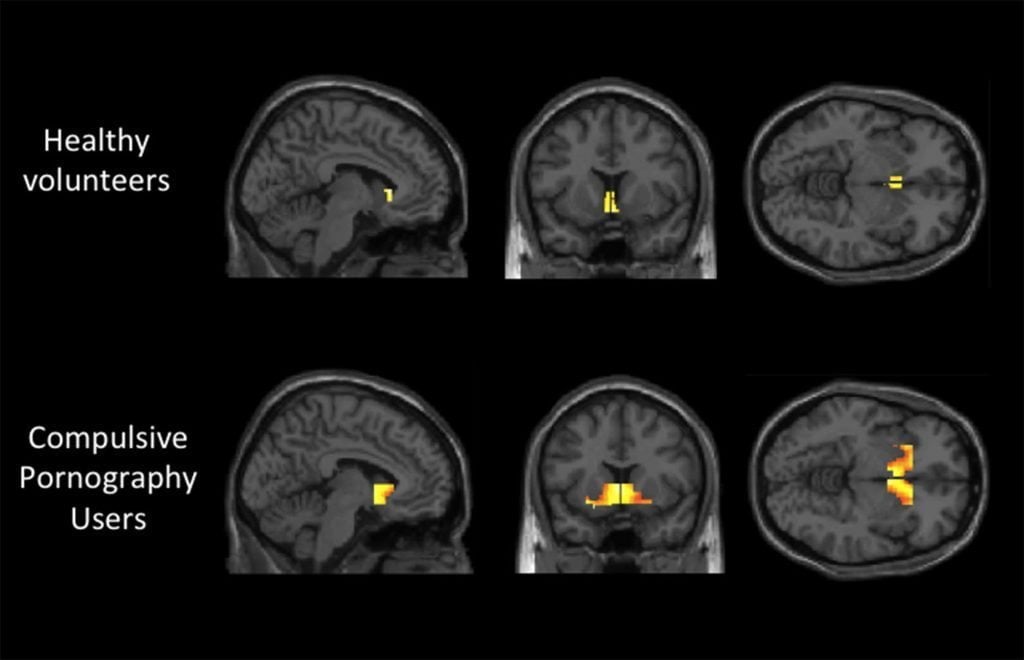

Porn overuse creates the same physical changes in the brain as food, heroin, or any other addiction.